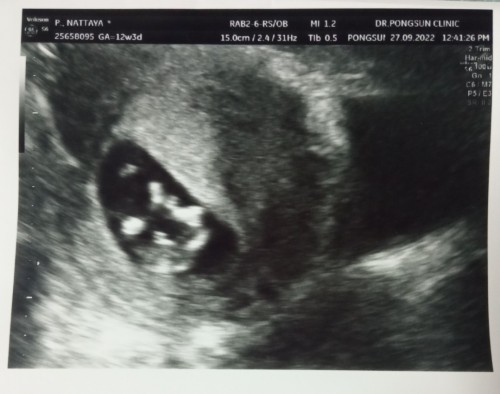

อัตราซาวเพศลูก

แบบนี้เพศหญิงหรือชายค่ะ หมอบอกว่าน่าจะเป็นชายเพราะเห็นเหมือนจู๋ พึ่ง 12 วีคจะเห็นเพศเร็วขนาดนี้เลยเหรอค่ะ

ถ้าเป็นเพศชายจริงๆ อาจจะเห็นก่อนได้ค่ะ

ปกติจะเห็นชัดช่วง4-5เดือนค่ะ